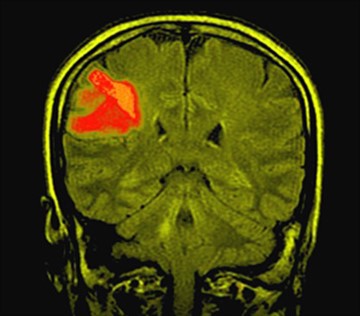

Признаки эпилепсии определяются теми участками головного мозга, в которых возникает патологический разряд. Обычно симптомы проявляются в нарушении тех функций, за которые отвечают пораженные зоны головного мозга.

При эпилепсии наблюдается аномально высокая электрическая активность нервных клеток головного мозга

Еще одной причиной, от чего возникает эпилепсия, является онкологическая патология в головном мозге. При таком заболевании мозговые ткани очень сильно меняются и повреждаются, что может дать некий толчок к развитию эпилепсии.

Клинические проявления эпилепсии во многом зависят от степени повреждения мозга и локализации очагов с повышенной эпилептической активностью. Лобная доля отвечает за выполнение произвольных движений.

При поражении затылочной доли мозга во время эпилептического приступа могут возникать вспышки света и цветные пятна перед глазами, а также зрительные галлюцинации. Возможна потеря цветового зрения и временная слепота.